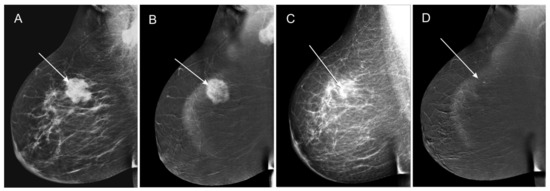

- Low-energy images from two consecutive contrast-enhanced spectral mammograms (taken before the start and at completion of neoadjuvant chemotherapy);

- Subtraction images from two consecutive contrast-enhanced spectral mammograms (taken before the start and at completion of neoadjuvant chemotherapy).